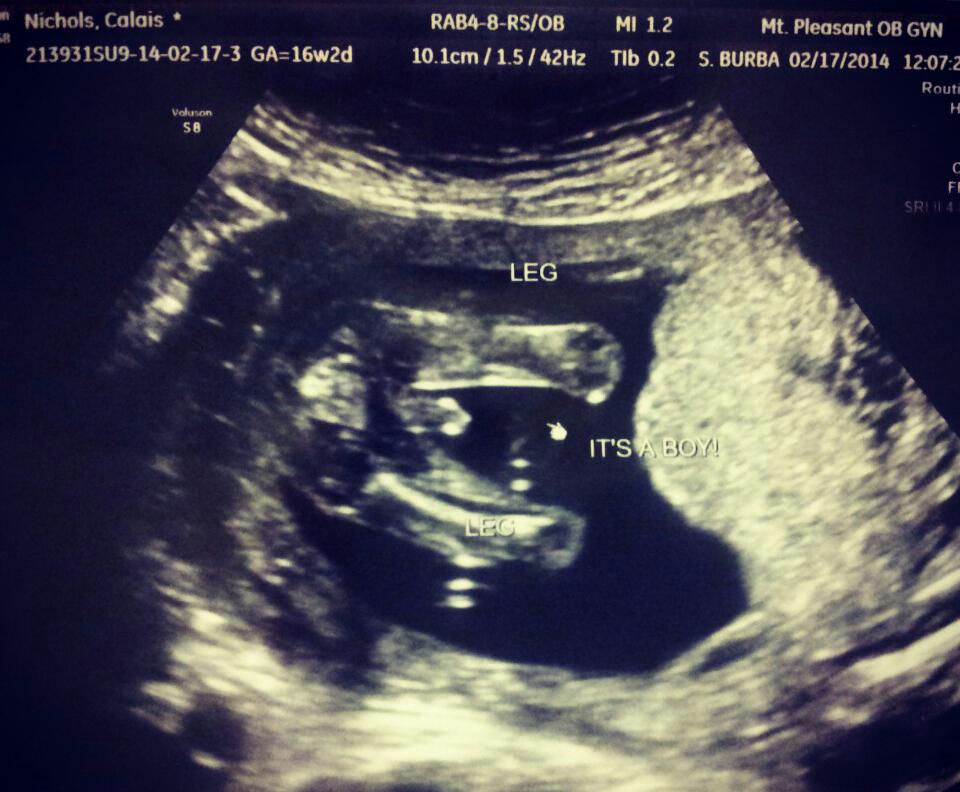

Tech said maybe boy...I'm afraid to hope too much..what do you ladies think?

It's a boy!!! Will post a pic when i get home :) thank you for your guesses, ladies!!!!